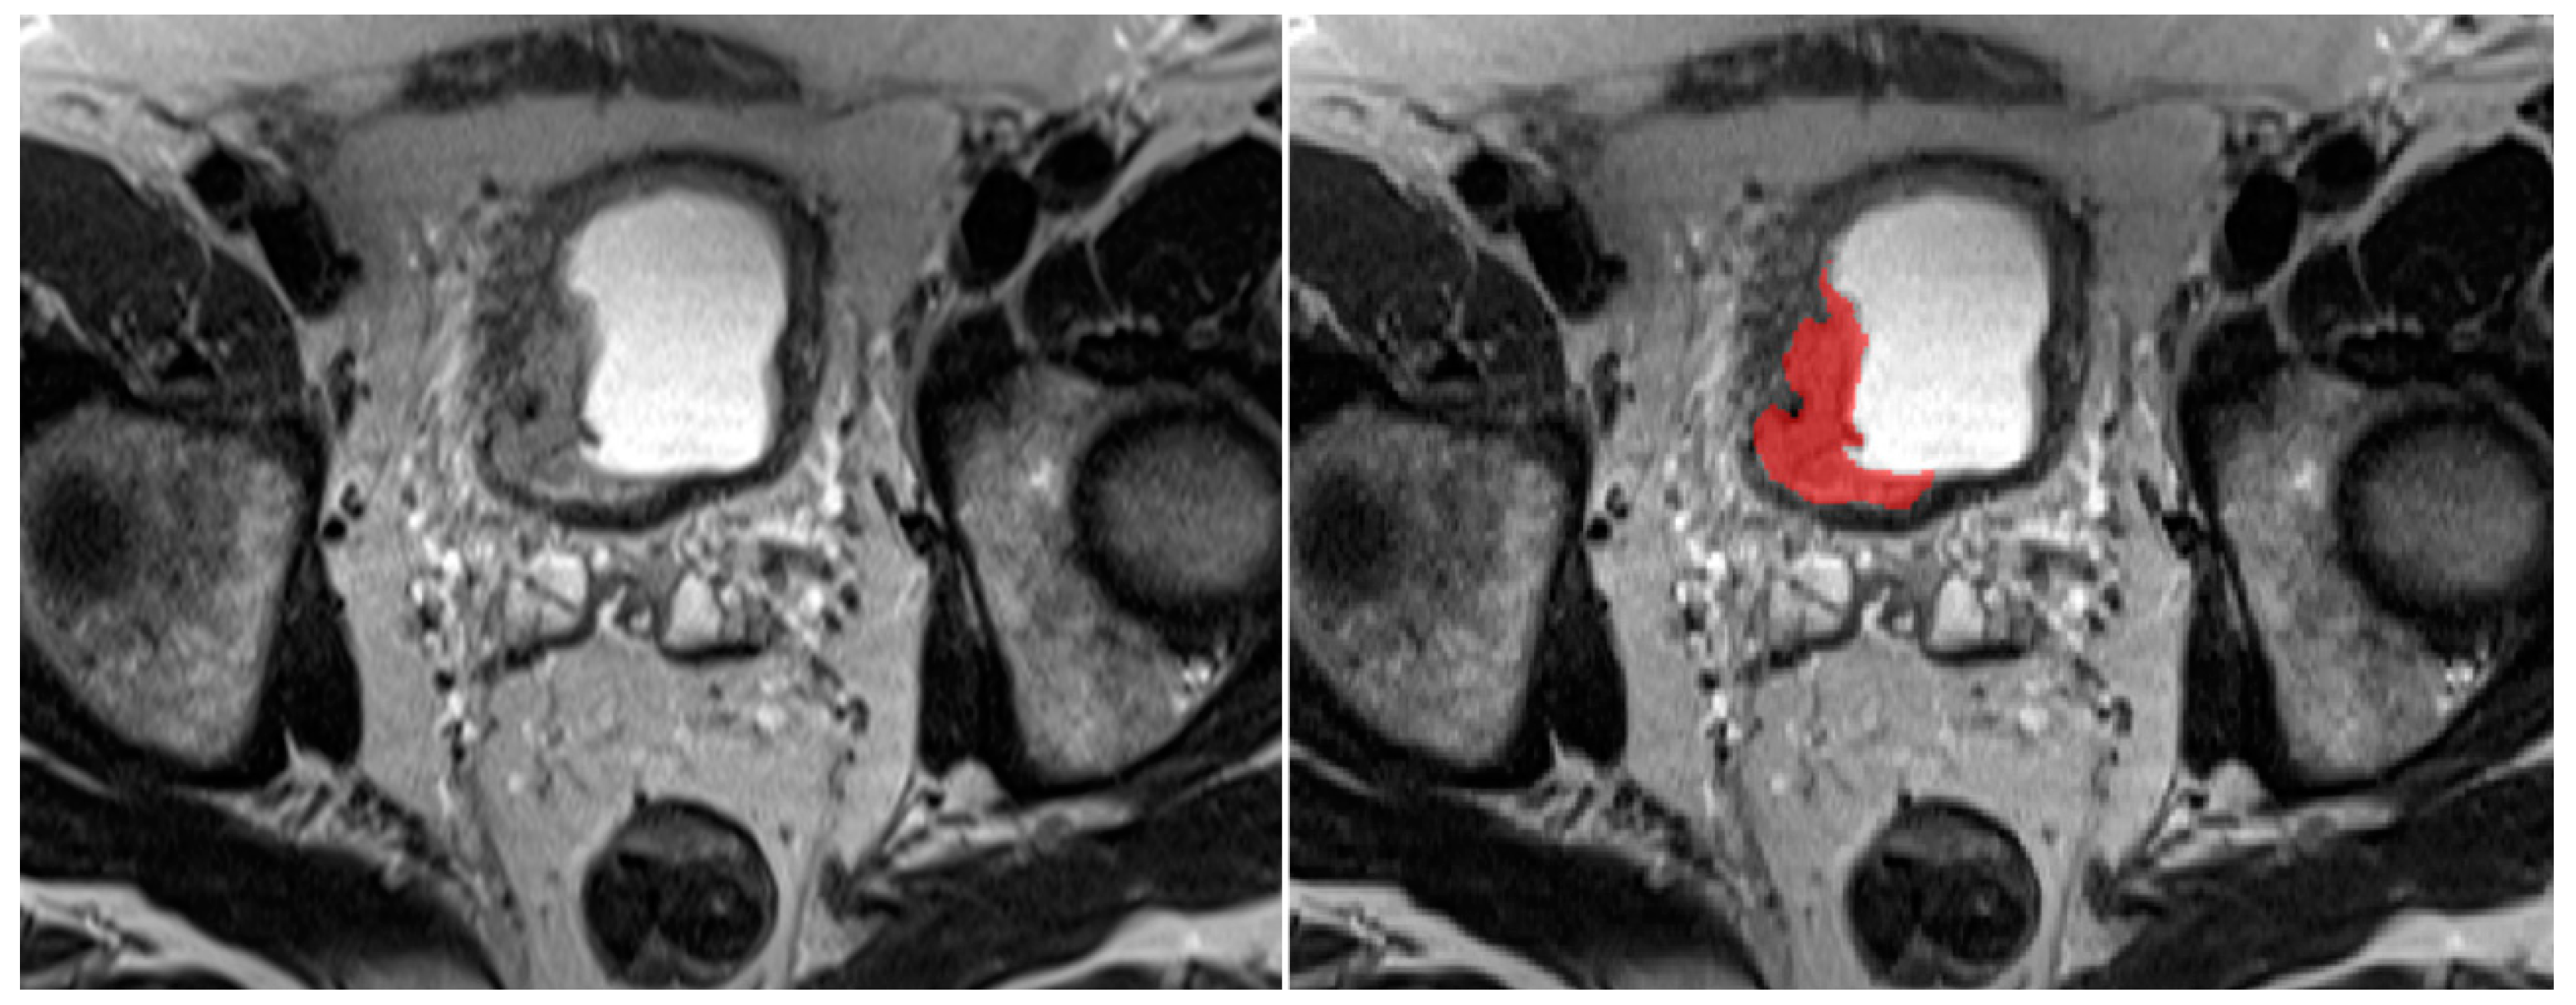

2.3. Image Segmentation

2.4. Deep Learning Models: Training and Evaluation